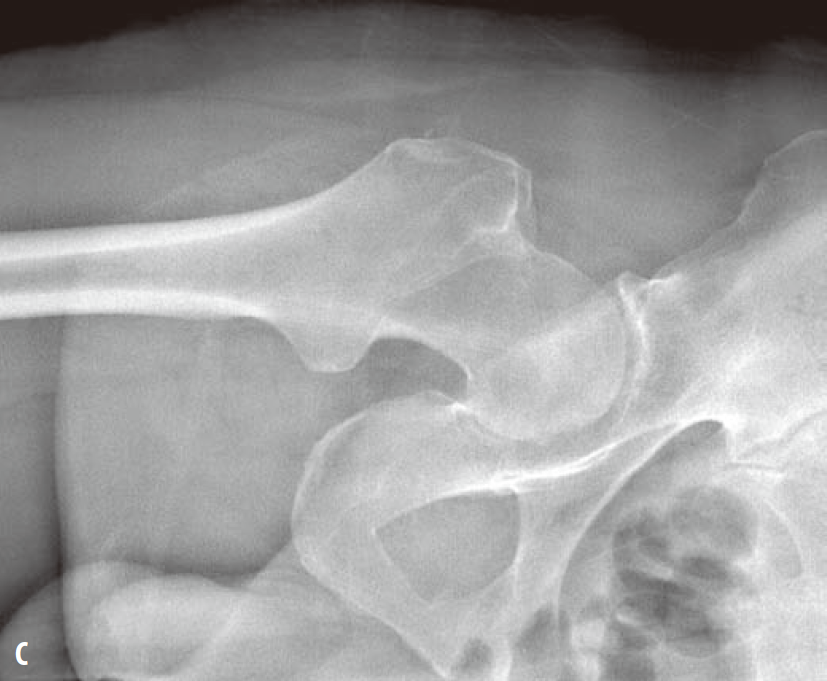

髓关节撞击综合征(femoroacetabular-impingement,FAI)是引起髋关节疼痛及髋关节进行性退行性变的一种常见病因。一般采用骨盆X线前后位照片筛查。骨盆照片时X线中心线应对准尾骨中心及耻骨联合,以保证骨盆不旋转。FAI主要分为3种类型:凸轮型、钳型和混合型。混合型FAI同时具有凸轮型和钳型的异常。凸轮型是股骨头颈连接处形成/发育异常所致,表现为股骨头颈连接处骨性隆起或“枪柄样”改变(缺乏正常的凹度)(图1)。钳型FAI表现为髋臼覆盖或位置异常,可根据在X线平片上见到深髋臼、髋臼前突或髋臼后倾的表现而诊断。深髋臼及髋臼前突X线表现为股骨头及髋臼相对髂骨坐骨线位置异常(图2)。髋臼后倾表现为交叉征、髋臼后壁征、坐骨棘突出征(图3)。

图1 左髋关节蛙式侧位X线片(A)显示股骨头、颈连接处异常隆起(箭),该骨质异常可引起凸轮型FAI。右髋关节前后位X线片(B、C)显示“枪柄样”畸形,其中旋转90°后的前后位X线片(C)可更直观地显示肌骨近端及股骨头所形成的“旧式手枪枪把”样外观